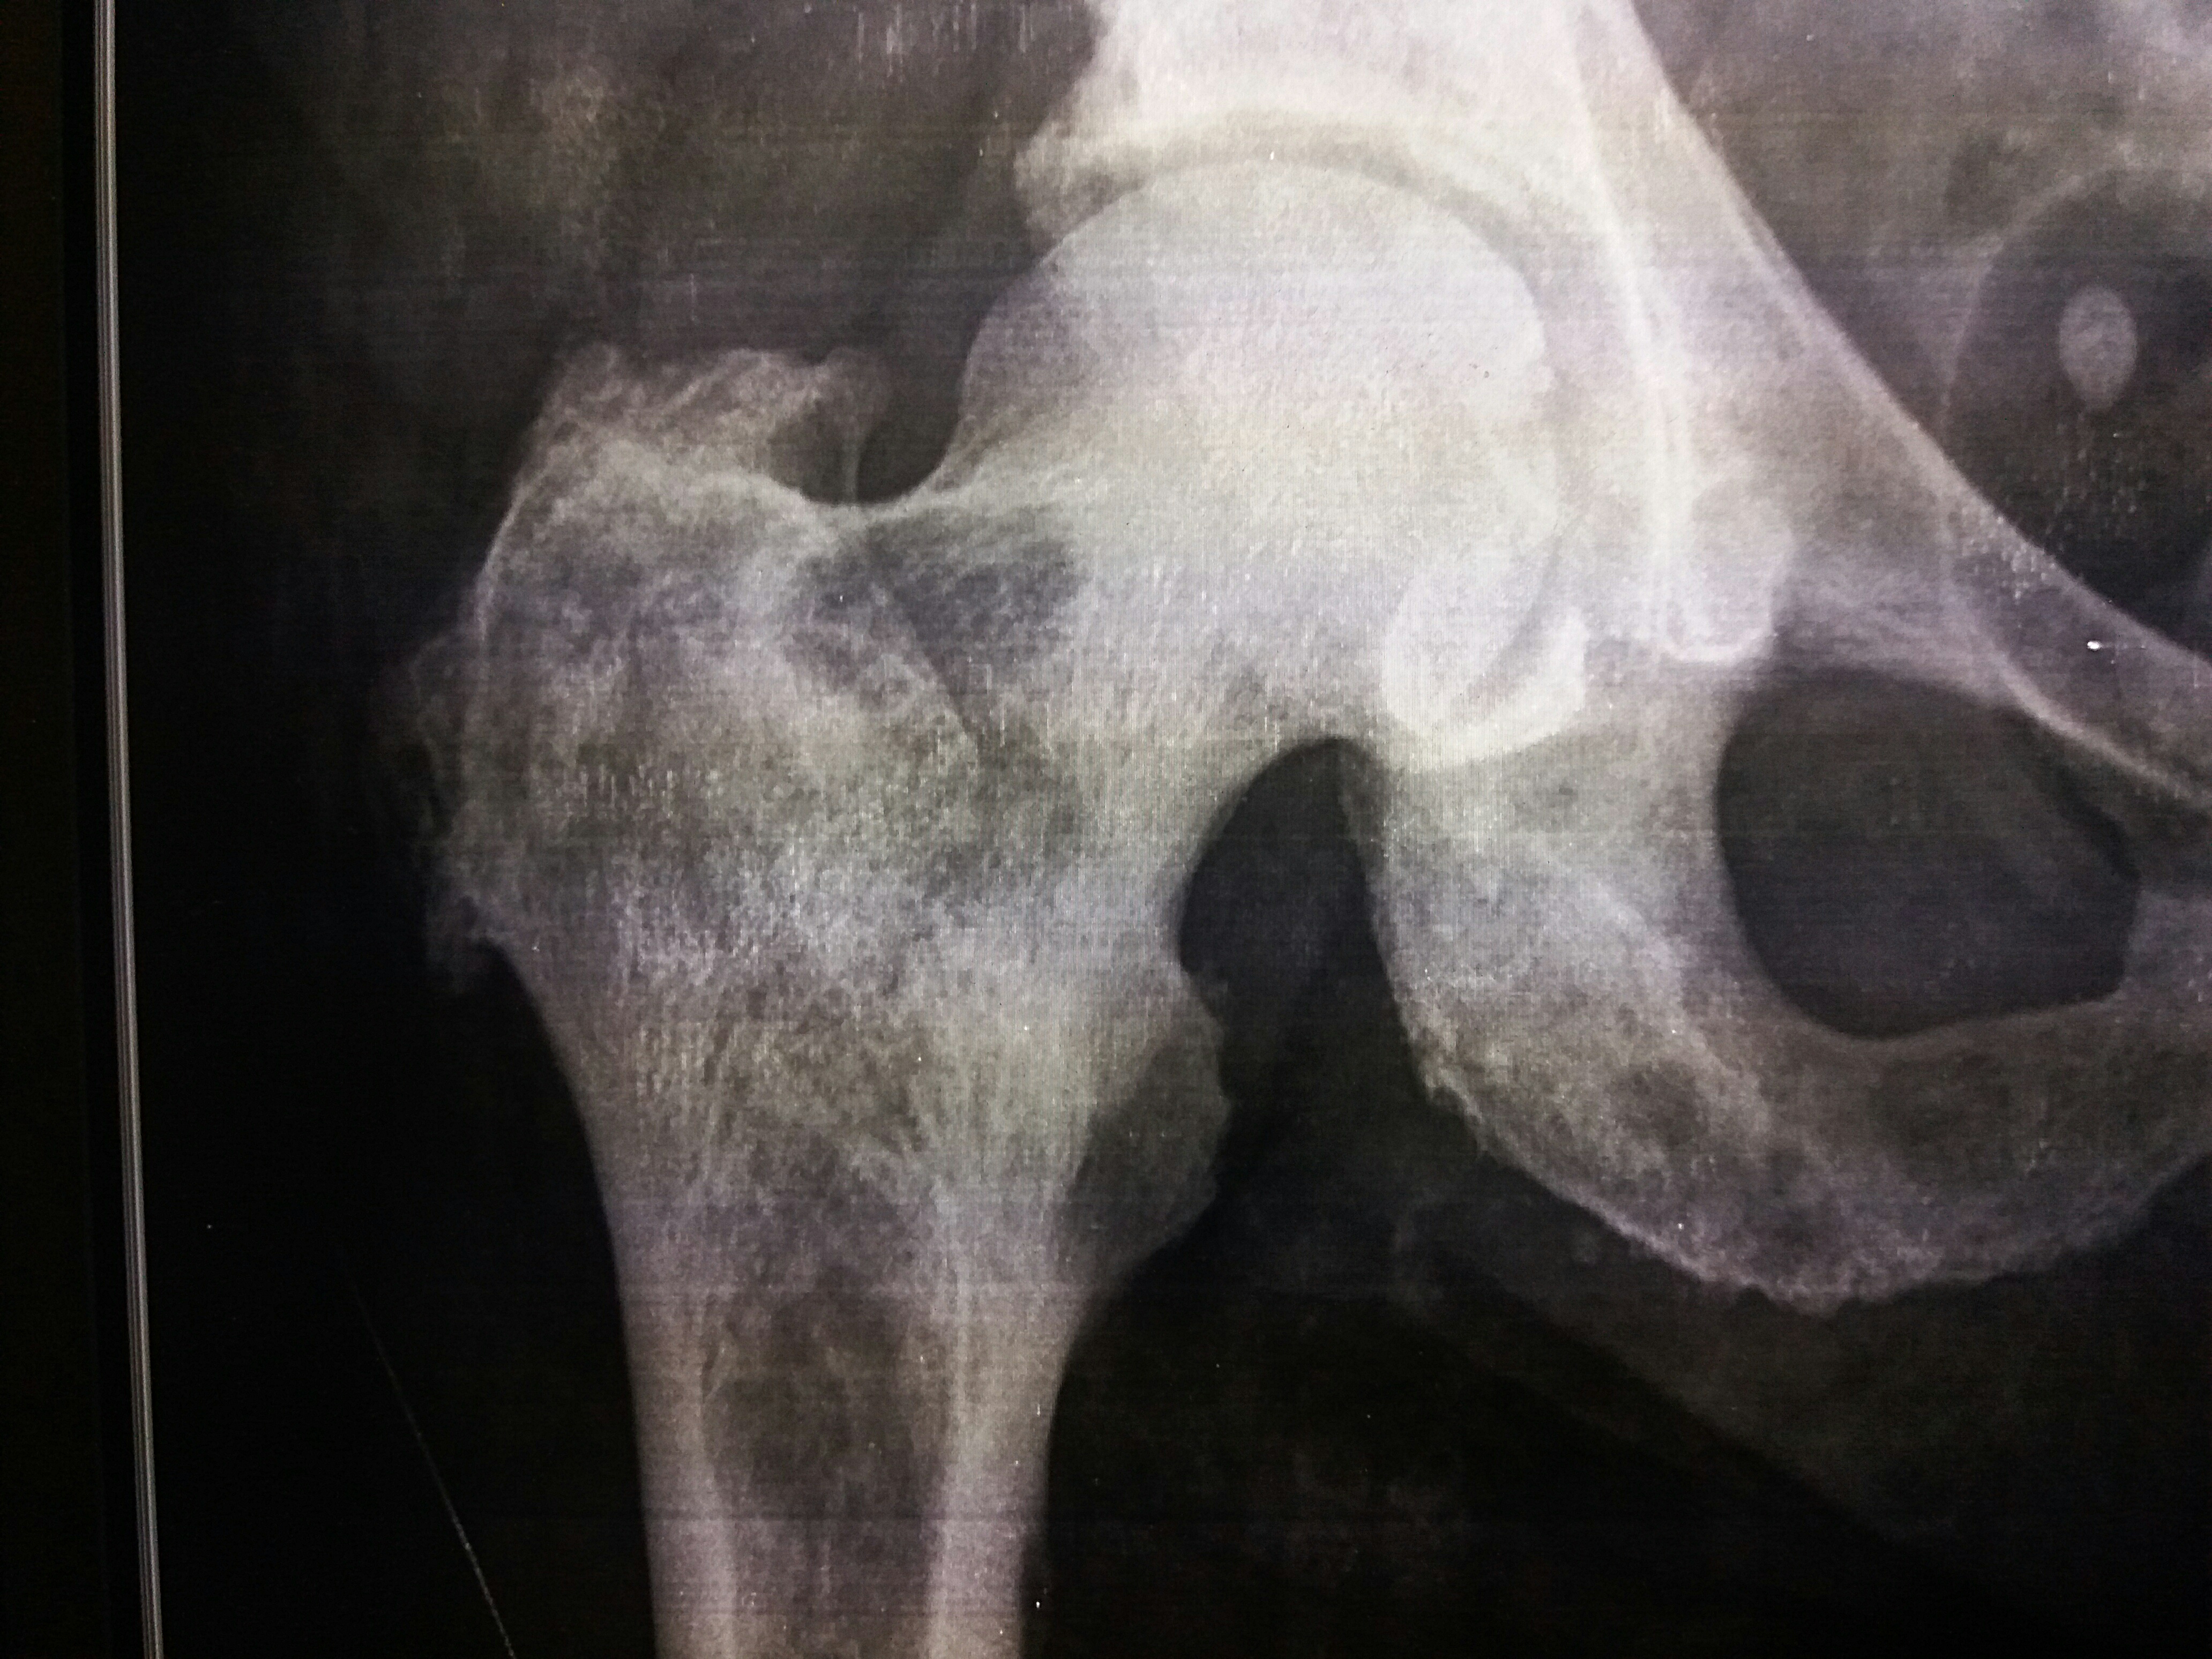

Рентгеновские снимки и визуализация болезни Педжета

Раздел: Мудрость в объективе